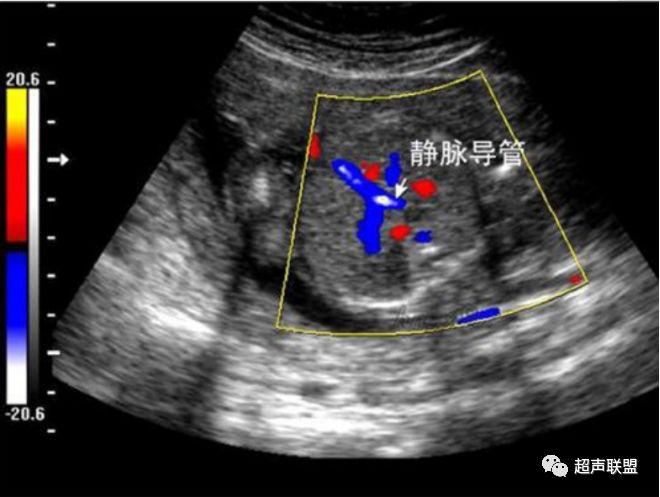

3 胎儿静脉导管

当右心负荷增大,心功能失代偿时,静脉回流受阻,静脉导管a波收缩期流速下降,血流消失甚至倒置。

5、静脉导管:a波消失或反向(见于严重的胎儿宫内缺氧);

3、静脉导管a波反向或消失;

图5 胎儿宫内正常静脉导管

图6 胎儿宫内缺氧时静脉导管a波反向